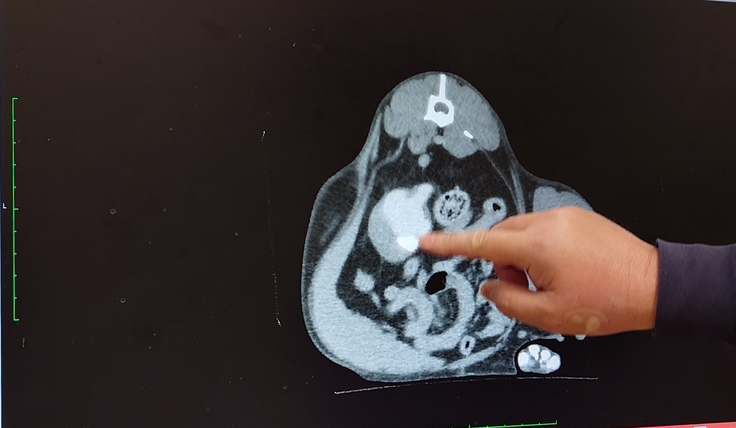

🐈造影剤を流して、腎臓から膀胱にちゃんと詰まらずに流れて行くか、膀胱から腎臓に逆流しないかを調べてもらいました。🐈

🐈尿管は拡張したままで腎盂も肥大したままではあるんだけど、造影剤は途中で詰まったり、逆流したりすることもなく、膀胱に流れていたから大丈夫とのことで安心しました🐈

🐈血液検査ではまた白血球等の数値が高くなっていて、また尿路感染を起こしているかもしれないと説明を受けました。🐈

🐈腎臓に関する数値は正常値だったので良かったです。🐈

今日はヨッちゃんが麻酔をしているから培養検査が出来ないので、こちらからもかかりつけの動物病院の先生に電話しておくので1週間後にかかりつけの動物病院で検査してもらってくださいとのことでした。もう1つ、ヨッちゃんは尿路感染を繰り返し起こしやすいかもしれなくて定期的に感染していないか検査をしていた方が良いことと、将来的に腎臓に膿が溜まってしまうかもしれない。もし、腎臓に膿が溜まってしまったら腎臓の摘出手術をすることになってしまうんです。という説明を受けました。もう1つの腎臓と膀胱をつなぐSUBシステムの手術の選択肢を言われるのかと思いきや腎臓摘出。えーー。。と複雑な感情になりました😨😵😱